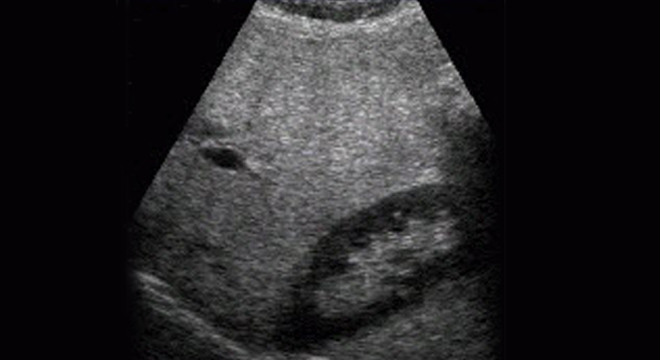

Fettleber: Ultraschall der Leber

• Ultraschall